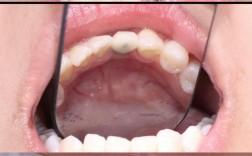

种植牙的基本原理与优势

种植牙是通过外科手术将人工牙根(种植体)植入牙槽骨,待其与骨组织结合后,再安装牙冠的过程,相比传统假牙,种植牙具有以下优势:

- 稳固耐用:种植体与牙槽骨结合后,能提供接近天然牙的咬合力,使用寿命可达20年以上(根据患者维护情况)。

- 保护邻牙:传统烤瓷牙需磨削健康邻牙,而种植牙独立支撑,不损伤其他牙齿。

- 延缓骨吸收:牙齿缺失后,牙槽骨会逐渐萎缩,种植体可刺激骨组织,减少骨质流失。